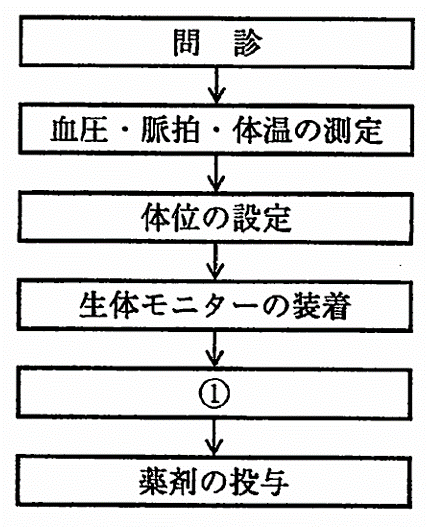

42歳の男性。多数歯のインプラント手術を予定している。強い不安を抱いているため、鎮静法で手術することになった。鎮静法の術式の流れを図に、使用する機器の写真を別に示す。①はどれか。 1つ選べ。

a.局所麻酔

b.静脈路の確保

c.酸素吸入の開始

d.鼻マスクの装着

解答を見る

b